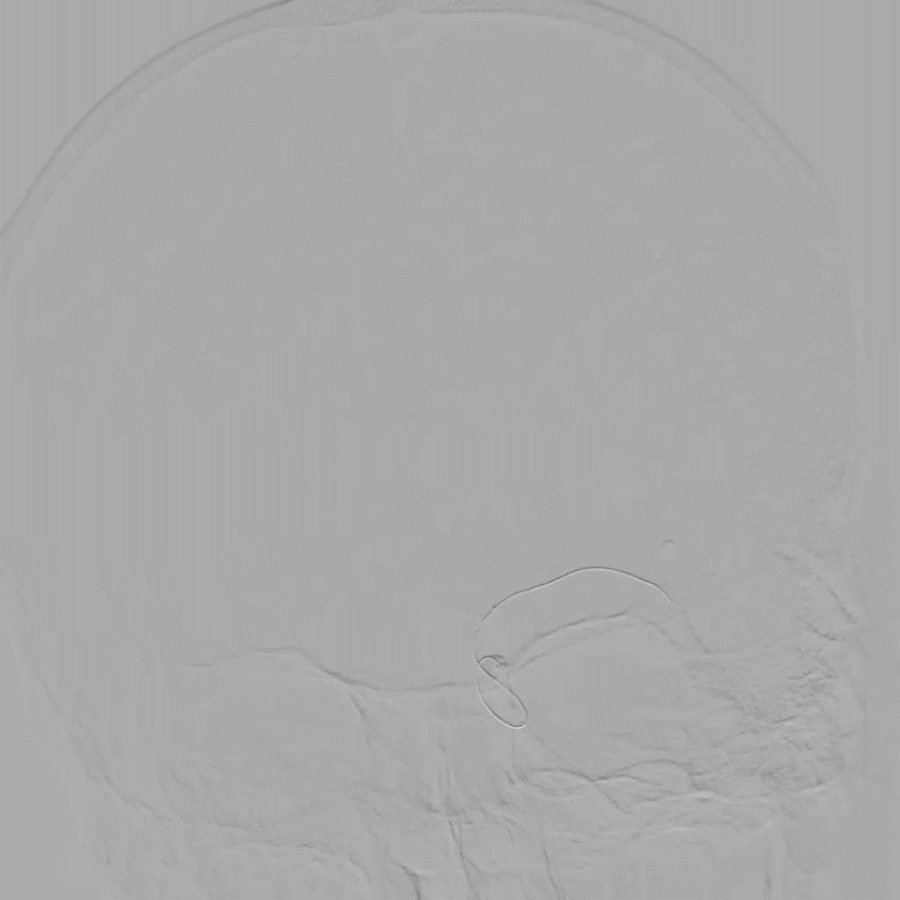

在泥鳅导丝导引下,用4F多功能管携8F导引导管直接进入左颈内动脉C1近段,血管迂曲8F导引导管无法进入左侧颈内动脉C1远端,遂取6F多功能管Navien,置于颈内动脉岩骨段,取微导丝在微导管辅助下小心通过血栓闭塞段到大脑中动脉M1,微导管在微导丝辅助下送大脑中动脉M1段,退出微导丝,将NeuroHawk®6030取栓支架在透视下放入左侧颈内动脉末段闭塞段并释放支架取栓,支架打开欠满意,闭塞段可见一重度狭窄,考虑血管慢性狭窄闭塞,予替罗非班0.625mg静脉推注后,持续静脉内0.4mg/h泵入,约8分钟后予撤出支架及微导管,此过程中用50ml注射器保持负压抽吸血液,取栓次数1次,取出一0.2cm×0.5cm血栓。

术中正侧位

复查造影提示左侧颈内动脉C7段重度狭窄,远端血流速度可,未见乏血管区,TICI分级3级(穿刺至再通1.28h),行DynaCT未见明显高密度影;观察10分钟、30分钟分别行脑血管造影提示左侧颈内动脉狭窄无明显回缩,远端血流可,继续替罗非班0.4mg/h持续泵入,从穿刺到结束手术1小时59分。术后患者苏醒满意,双侧瞳孔等大,疼痛刺激右侧肢体可见少许活动。

术后正侧位